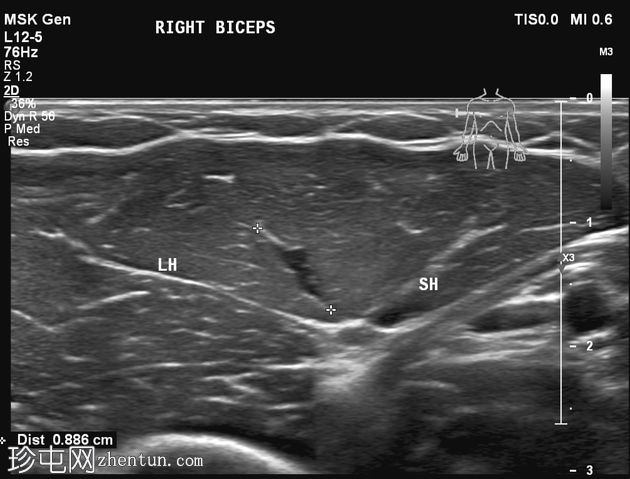

静息状态:肱二头肌短头和长头肌肉结构正常。肌腱和肌腱连接处完整,仅有轻微的断裂或积液迹象。

肘关节屈曲及肌肉收缩动态成像:肱二头肌短头和长头肌纤维之间出现充满液体的裂隙,提示局部肌筋膜分离/拉伤。未见肌纤维全层撕裂。肱二头肌远端止点正常。

诊断:肱二头肌短头和长头之间的动态肌筋膜损伤,收缩时裂隙内积液。